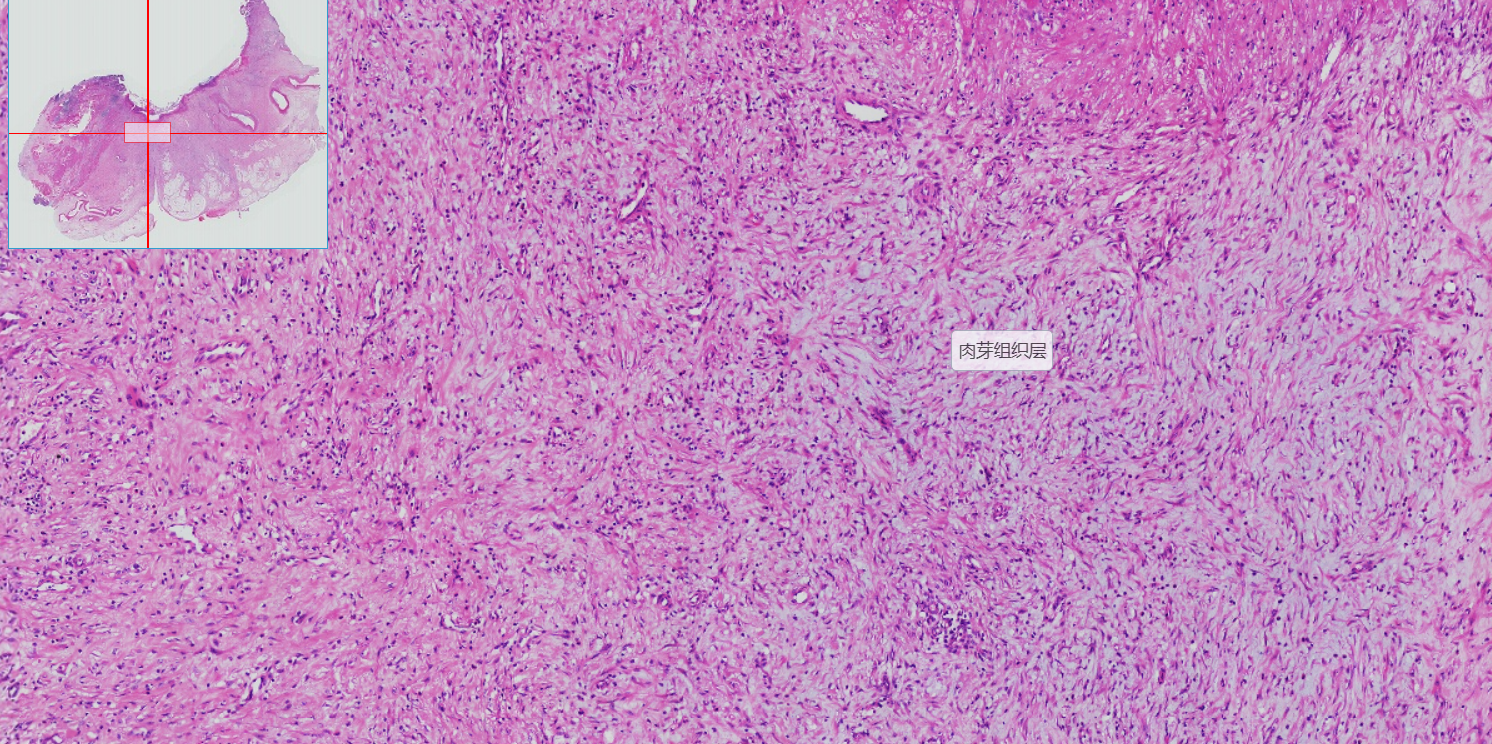

5 胃溃疡

4.巨噬细胞吞噬坏死物